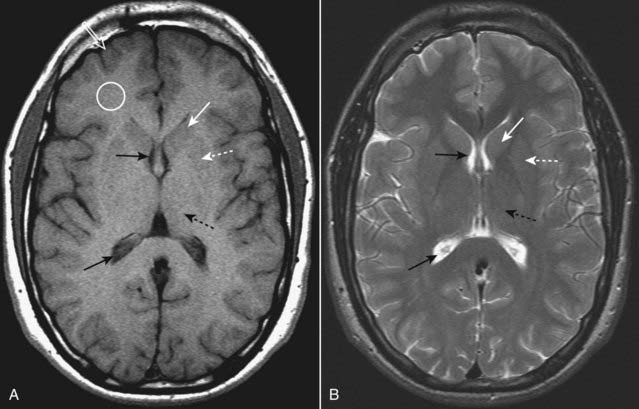

image MR is the study of choice in identifying diffuse axonal injury.

The small petechial lesions may be bright on T1-weighted images.

The most common findings are multiple bright areas on T2-weighted images at the temporal or parietal corticomedullary junction or in the corpus callosum (Fig. 25-13)

image

Figure 25-13 Diffuse axonal injury, MRI.

These images were obtained using a pulse sequence similar to T2 but with suppression of the bright signal from CSF, which enhances areas of edema (that appear bright). (A) and (B) are axial images demonstrating multiple foci of abnormal increased signal at the gray-white matter junction (solid white arrows) and within the splenium of the corpus callosum (solid black arrow) in a patient with diffuse axonal injury.